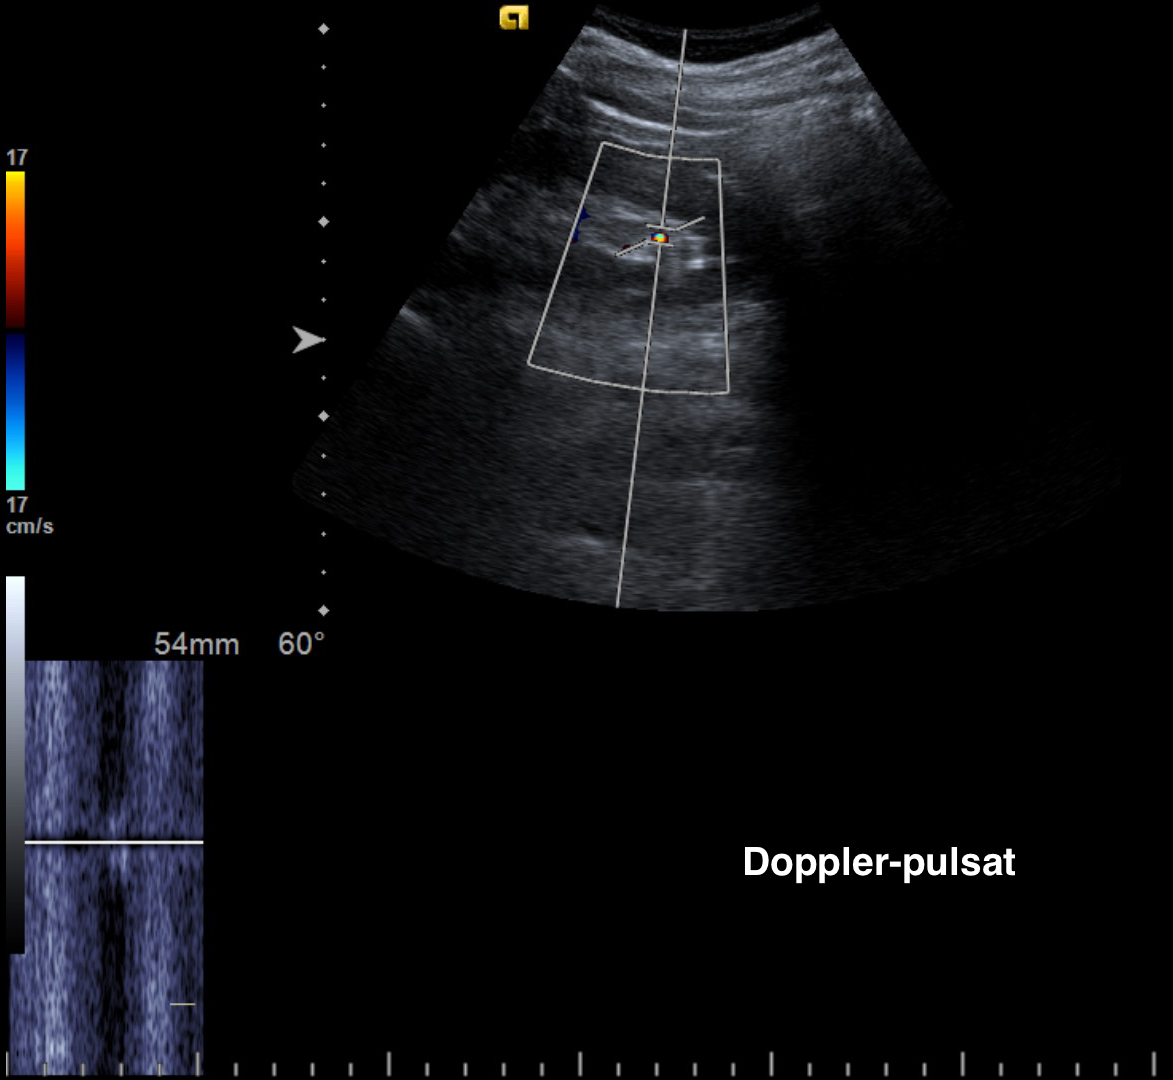

ECOGRAFIE: (imaginea 1) formațiune tumorală renală stângă cu dimensiuni de aprox 3.18/3.4/3.31 cm, volum de aprox 19.1 cmc, cu un contur polilobat, structura inomogenă prin prezența de arii hipoecogene și discrete benzi hiperecogene, cu vascularizație intensă evidențiată în Doppler color și prin reconstrucția 3D din power Doppler.

Examinarea renală trebuie mereu să includă baleiajul parenchimului renal în modul Doppler. Prin această tehnică putem diagnostica microcalculii renali care nu sunt vizibili în modul B.

De exemplu, în cazul pacientei de mai jos, s-a evidențiat un microcalcul polar inferior, cu diametrul de 4 mm, care generează ring-artefact/ twinkling artifact (mozaicism neomogen) și semnal caracteristic în modul pulsat (semnal care nu corespunde nici tipului arterial, nici tipului venos + se aude un zgomot puternic, deranjant). După cum puteți observa, microcalculul nu e vizibil cert în modul B (este prea mic pentru a da con de umbră posterior).

Așadar, aceasta este singura modalitate ecografică de a diagnostica microlitiaza.

„Diagnostic diferențial al artefactului”:

- turbulență focală? – prin baleiaj observăm că nu există continuitate, deci nu e vorba de arborele vascular;

- placă arterială calcară? – în această situație, morfologia artefactului ar fi una liniară și cu siguranță vom observa și modificări de ecogenitate în parenchimul renal (bineînțeles, ne ajută și clinica pacientului).